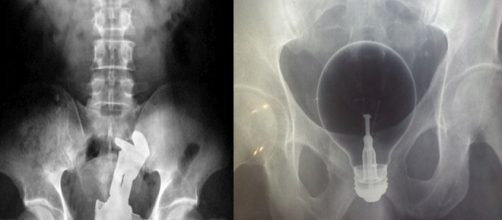

7- Um vibrador “perdido” e uma pinça para tentar retirar o vibrador, que também acabou se perdendo.

10- Uma lâmpada muito resistente.